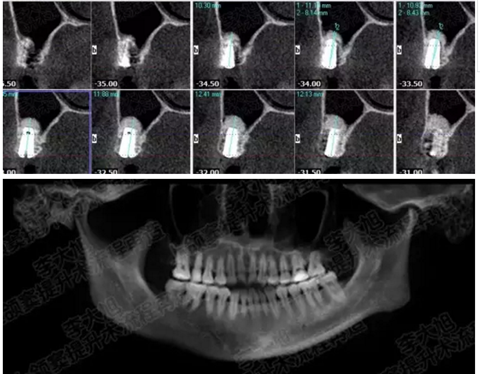

病例一

上頜竇多分隔3mm

05.png

提升8mm

06.png